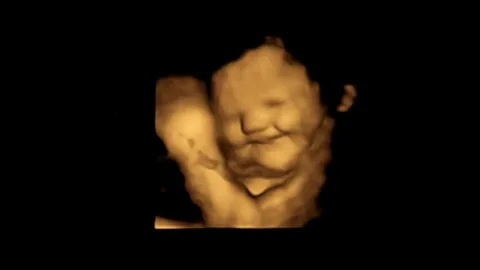

สุดทึ่ง ผลศึกษาใหม่อังกฤษ พบแม่ตั้งครรภ์ กินแครอท ทำทารกยิ้มอารมณ์ดี